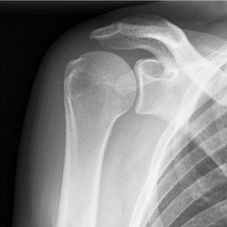

De gewone of anatomische prothese is een oplossing voor een versleten of artrotische schouder waarbij enkel het kraakbeen kapot is en de pezen volledig intact.

Bij deze prothese worden de kraakbenige oppervlaktes vervangen door metaal en kunststof.